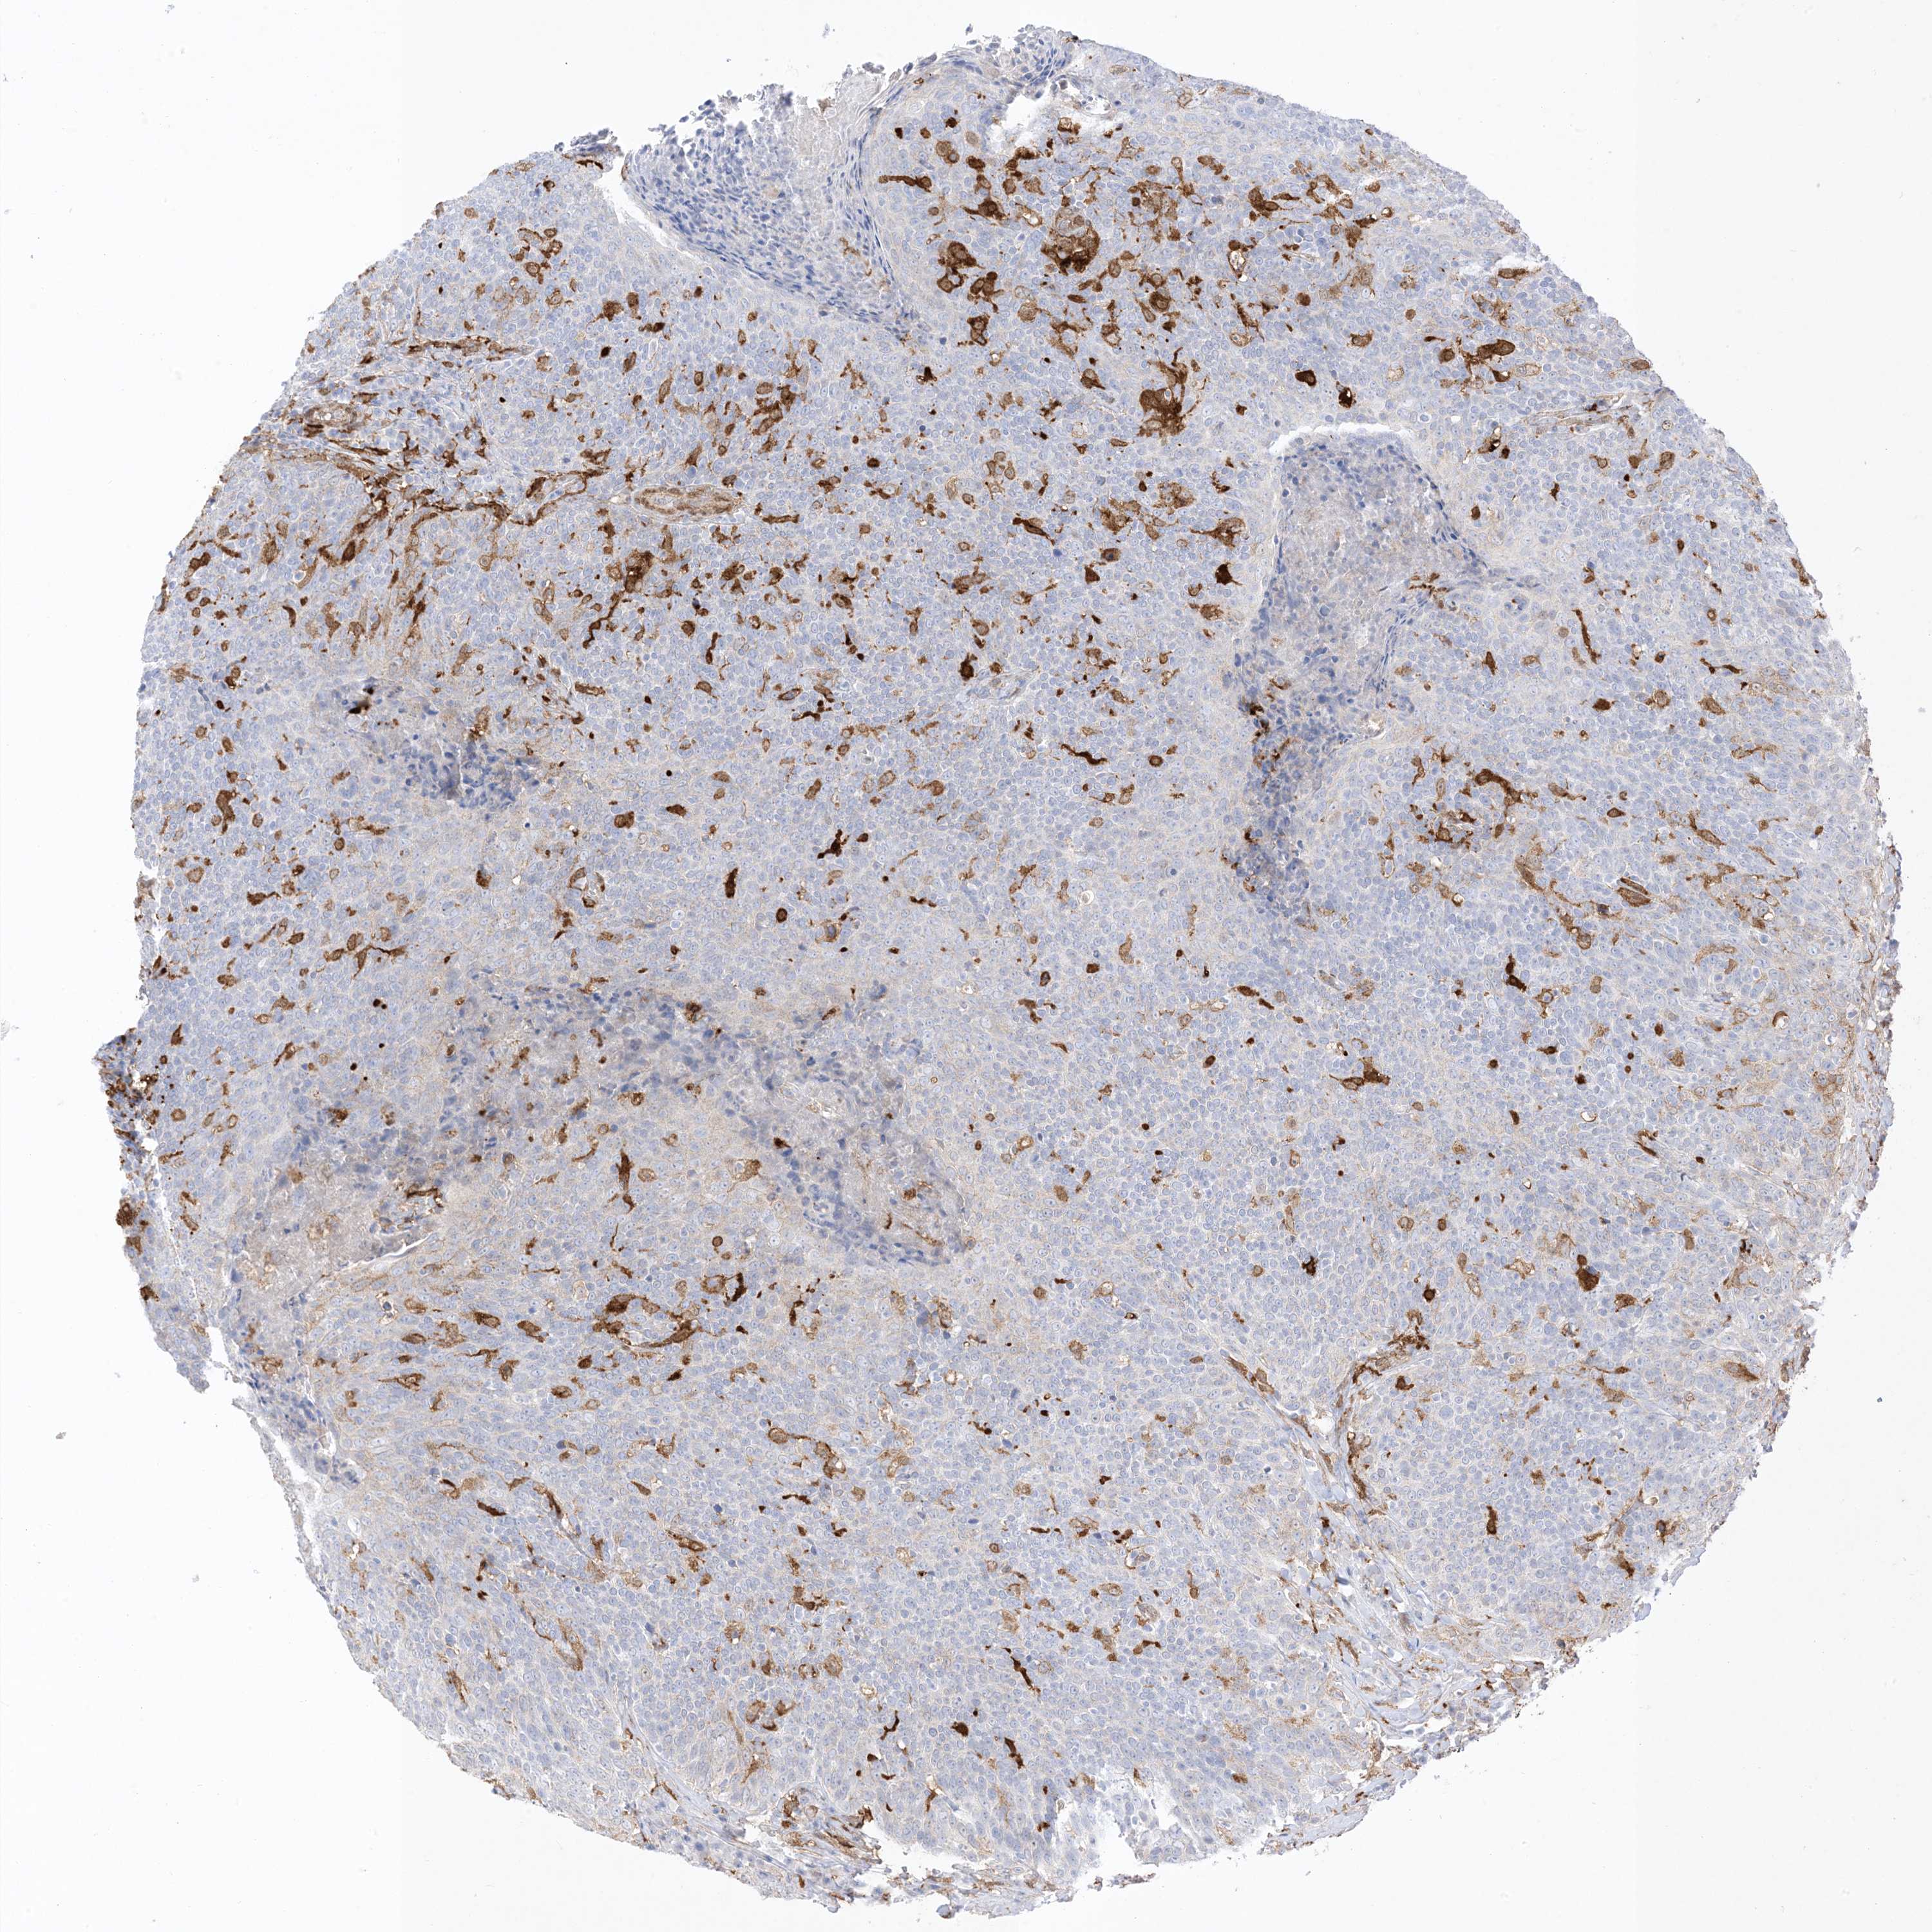

HEAD AND NECK CANCER - Protein expressioni

A mouse-over function shows sample information and annotation data. Click on an image to view it in a full screen mode. Samples can be filtered based on level of antibody staining by selecting one or several of the following categories: high, medium, low and not detected. The assay and annotation is described here.

Antibody stainingi

Antibody staining in the annotated cell types in the current human tissue is reported as not detected, low, medium, or high, based on conventional immunohistochemistry profiling in selected tissues. This score is based on the combination of the staining intensity and fraction of stained cells.

Each image is clickable and will lead to virtual microscopy that enables deeper exploration of all samples and also displays staining intensity scores, fraction scores and subcellular localization as well as patient and tissue information for each sample.

Antibody HPA054026

Antibody CAB010823

Antibody CAB016728

Antibody CAB036009

Staining

High

Medium

Low

Not detected

Intensity

Strong

Moderate

Weak

Negative

Quantity

>75%

75%-25%

<25%

None

Location

Nuclear

Cytoplasmic/membranous

Cytoplasmic/membranous,nuclear

Squamous cell carcinoma, NOS

Adenocarcinoma, NOS

Squamous cell carcinoma, metastatic, NOS

Adenoma, NOS